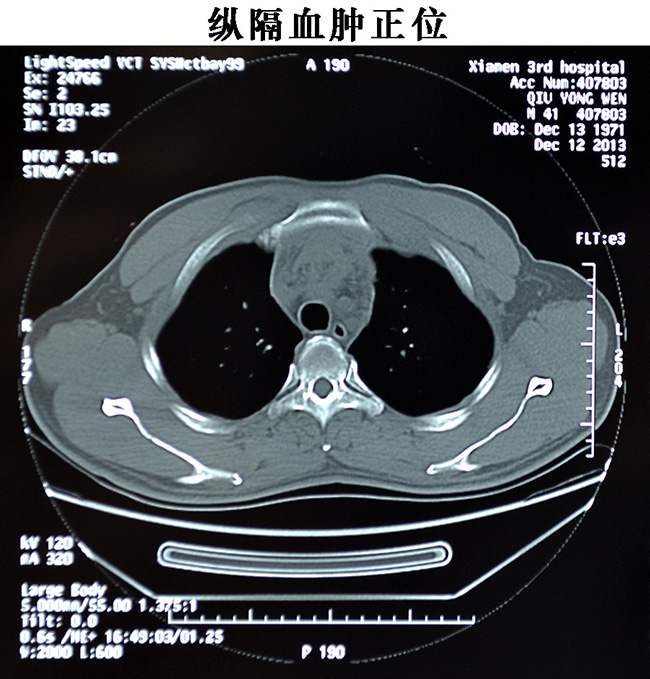

胸心外科成功抢救一名胸骨横断骨折合并纵隔血肿患者

昨日下午15时,患者邱某某42岁骑电动车上班途中,不慎撞上隔离护栏,当即感觉胸部刺痛,呼吸困难,急送伦理片,给胸部CT检查诊断为“纵隔血肿”后收入胸心外科,经详查发现患者胸部轻度肿胀,胸骨压痛剧烈,呼吸费力,心率达120次/分,胸心外科医师认真分析病情后高度怀疑胸骨骨折,急行胸骨CT三维重建。18时左右,CT结果证实胸骨横断骨折,骨折两端分离1CM,随呼吸浮动,纵隔后大血肿,情况危重,如不及时处理,胸骨骨折将严重患者呼吸功能,纵隔血肿继续肿大可压迫心脏,导致血压下降,甚至心脏骤停,后期还可能造成纵隔感染等情况,经耐心细致地与家属沟通,积极的术前准备后,当晚21时,急诊行胸骨骨折内固定+纵隔血肿清创术,1小时30分钟后手术顺利结束,患者生命体征平稳,正在康复中。